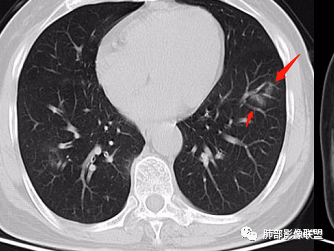

2、CT表现为两肺下叶结节影、斑片影、磨玻璃影,沿支气管血管束分布,部分支气管壁显示增厚。粗略一看部分病灶内似可见“细网格影”,但是仔细观察,可发现此“细网格影”不同于我们常见的“细网格影”,尤其是右肺下叶病灶,可以观察到病灶内部的网格上有高密度结节感或颗粒感,部分层面见“反晕征”,且反晕的边缘亦可观察到结节感。未见胸腔积液。

2、但影像学具有一定的特征性,病变一般沿支气管树分布或小叶分布,一般上肺多于下肺。部分病例呈双肺“雪花样”分布,较有特点。部分病例可表现为“反晕征”。除以上表现外,间质性肺结核还可以表现为:1 肺小叶间质内异常,表现为小叶间质内网状影,呈网结节样改变,与正常肺分界较清晰是其特点。2 支气管血管束增粗和小叶间隔增厚。3 磨玻璃影。

2、好发部位与其它结核类似,上叶及下叶背段为主。 3、烟花征,反晕征,环呈结节状,可以伴随空洞,树芽征,结节灶,胸水。(反晕征:一般周围实性环形高密度影,中央呈低密度;一般环超过圆的3/4,结核的环主要是小叶核心结节组成,类似于多发树芽征聚集,边缘结节感。中央的晕:可以是腺泡结节,树芽征,细网状,磨玻璃影,很少正常,主要成分是小叶内间质增厚、小叶核心结节、肺泡内病变。)其实也体现了结核的多灶性、多态性特点。